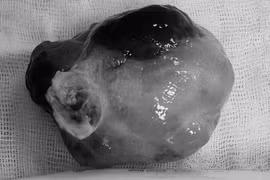

Chiều 17-6, Bệnh viện Đa khoa Xuyên Á (BVXA) thông tin đã phẫu thuật thành công cắt khối u trung thất (u ở phần lồng ngực giữa hai lá phổi) kích thước rất lớn 13x15x18 cm.